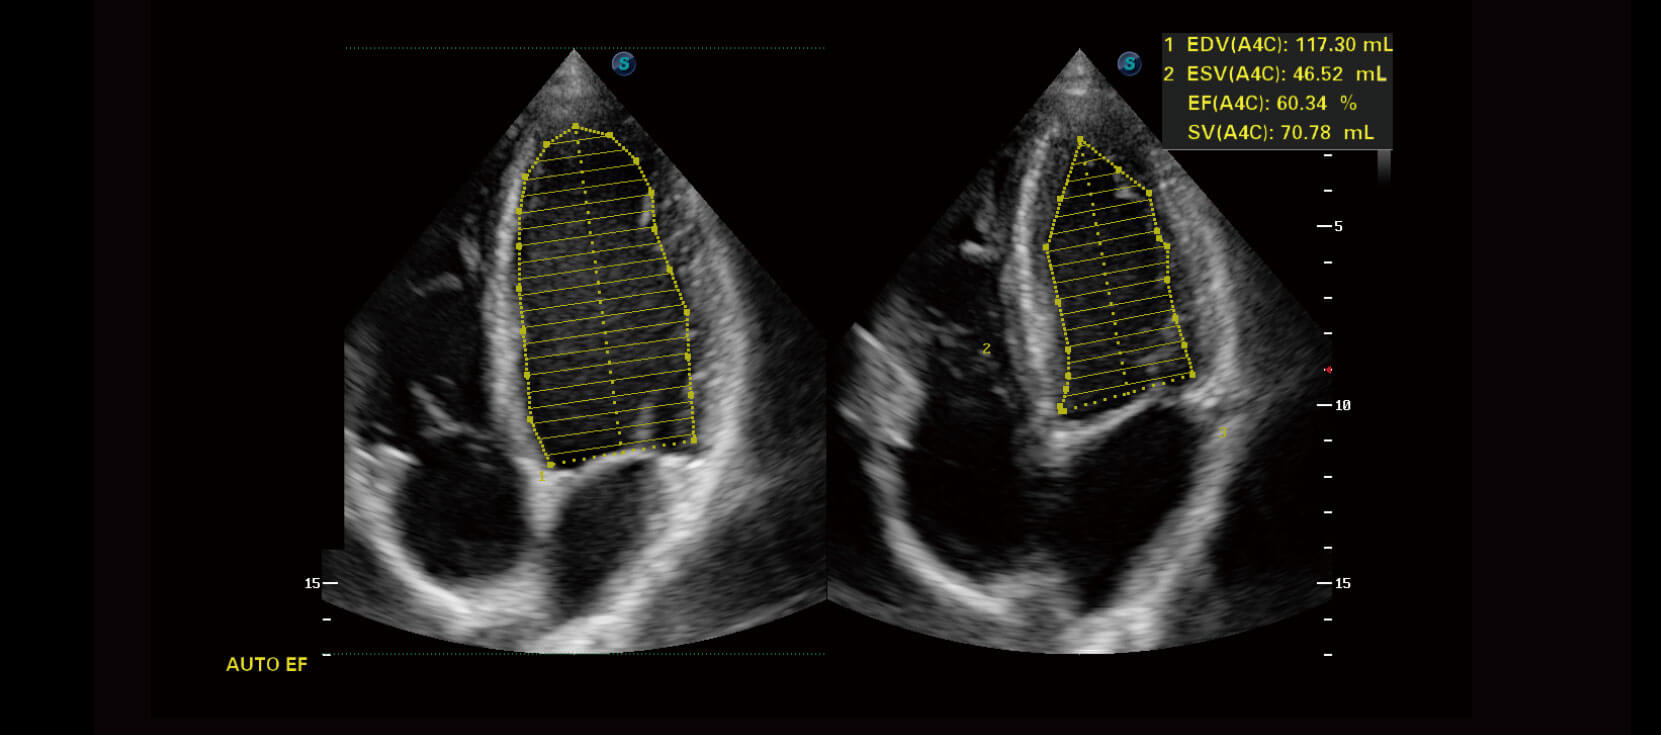

Auto EF

Nhận dạng và tự động tạo đường viền của các cấu trúc giải phẫu

Đạt hiệu quả cao với kết quả đo được hiển thị trong một giây